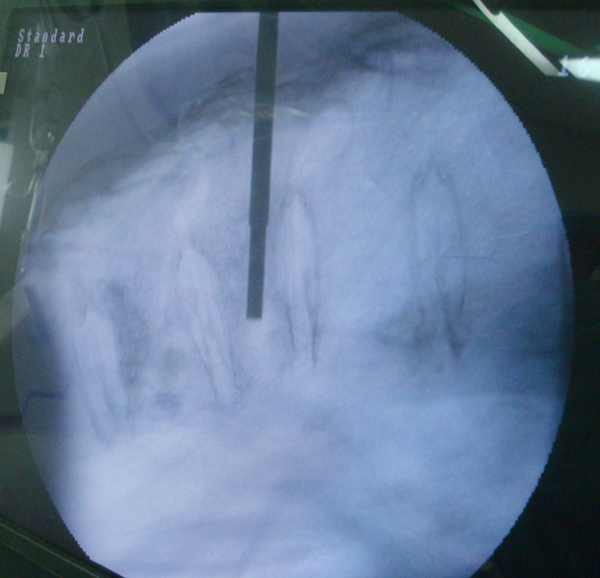

病例:李大伯,80多岁,患有高血压20年了,最近又发现有糖尿病,几天前,腰背部出现疼痛,并向两侧肋下放射痛,尤其在睡觉翻身和起床坐起活动时疼痛加重。到广西中医学院附属瑞康医院照片检查后,诊断为老年性骨质疏松症并胸11、12压缩性骨折。如果李大伯按照传统保守治疗方法——卧床,患者卧床至少要6周以上,随着卧床时间的延长,相关肺炎、泌尿系感染、下肢深静脉栓塞、褥疮等并发症便会接踵而来,将威胁她的生命。如果按照传统手术治疗,创伤大,出血量多,患者年龄高,还有高血压和糖尿病,手术风险非常大,随时危及生命。广西中医学院附属瑞康医院脊柱微创外科陈远明博士介绍,如果使用现在脊柱微创外科技术,患者在局部麻醉下,用一根针在腰背部穿至骨折椎体,注入胶水状的“骨水泥”,几分钟后“水泥”凝固,压缩椎体高度部分恢复,而骨折的椎体也因“骨水泥”填充而稳定,骨折引起的剧烈疼痛就会明显减轻,甚至消失。李大伯最后按照陈主任介绍方式做了该微创手术,当天疼痛消失,第二天下活动无不适,第三天康复出院,背上仅仅留下两个穿刺针眼。

椎体成形术中